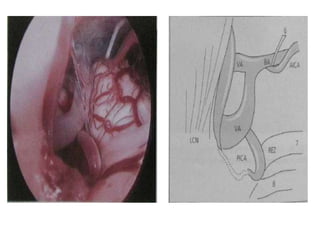

a,b Intraoperative image of the fenestration of deep cystic membrane using different microsurgical

instruments (forceps and scissors). Asterisks posterior communicating artery and anterior choroidal

artery. c Fenestration of the cisternal layer (cross Liliequist’s membrane). d Intraoperative picture at the end

of the procedure